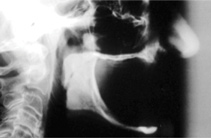

The Toronto Conference in 1982, chaired by Professor George Zarb and presented by Professor Per-Ingvar Brånemark, was a seminal event that changed edentulous treatment planning concepts irrevocably. No longer was it necessary to rebuild lost bone through grafting alone in either arch. The severely atrophic mandible, for example, could be treated with as few as four implants used to support a bone-sparing prosthesis through integrated tooth analogs, as demonstrated in Figure 1 through Figure 3. Here, an 81-year-old patient presented with severe mandibular atrophy (Figure 1) from denture wear since a very young age and had a history of being unable to manage a mandibular prosthesis despite numerous attempts at new denture construction. Four vertical machined-surface osseointegrated implants were placed in 1983 by Professor Brånemark, and all four penetrated the inferior cortex up to 3 mm to 4 mm in depth, as shown on the immediate postoperative panoramic film (Figure 2). At 4 years and 5 months, reparative bone had formed to the apices of all implants (Figure 3), and all of them remained in uncompromised function until the patient passed away at age 90.

Fig 3. At 4 years and 5 months follow-up, reparative bone had formed to the apices of all implants.

Figure 3